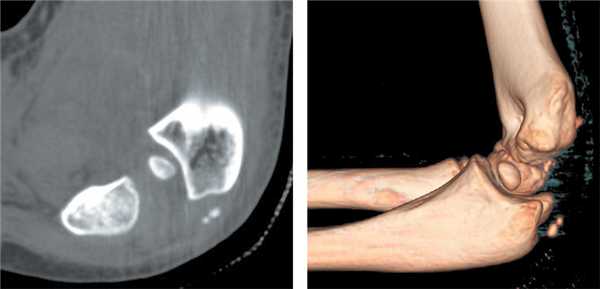

После утверждения протокола исследования местным этическим комитетом из базы данных детской больницы Salesi были отобраны записи всех пациентов, которые в период с 1 января 2014 г. по 31 декабря 2017 г. обращались в отделение неотложной помощи по поводу ПМН. Хирург-ортопед проводил классификацию ПМН по Watson-Jones (WJ) [9] и Papavasiliou [10]. Критериями включения в данное исследование были ПМН с внутрисуставным ущемлением в локтевом суставе, изолированные ПМН (III тип по WJ) или ПМН с вывихом предплечья (IV тип по WJ). В исследование включено 13 детей (5 мальчиков и 8 девочек), средний возраст которых составил 10,9 года (8-13 лет). Согласно записям в исследование было включено 6 пациентов с изолированным ПМН с внутрисуставным ущемлением в локтевом суставе (III тип по WJ) и 7 пациентов с ПМН с внутрисуставным ущемлением в локтевом суставе после закрытой репозиции по поводу сопутствующего заднелатерального вывиха предплечья (IV тип по WJ) (рис. 1). У 6 пациентов до операции наблюдалась парестезия в зоне иннервации локтевого нерва. В отделении неотложной помощи была выполнена рентгенография локтевого сустава в стандартных переднезадней и боковой проекциях. Для подтверждения внутрисуставного ущемления до операции одному пациенту была проведена трехмерная компьютерная томография (рис. 2). Перед исследованием было получено информированное согласие родителей/опекунов пациентов на использование медицинских карт их детей. Среднее время наблюдения составило 24,1 мес. (11-44 мес.).

Рис. 1. Пациент С. Вывих предплечья с внутрисуставным ущемлением медиального надмыщелка: а, б — рентгенограмма вывиха предплечья; в, г — рентгенограмма после устранения вывиха предплечья с внутрисуставным ущемлением медиального надмыщелка

Рис. 2. Пациент С. Компьютерная томограмма с 3D-реконструкцией после устранения вывиха: внутрисуставное ущемление медиального надмыщелка